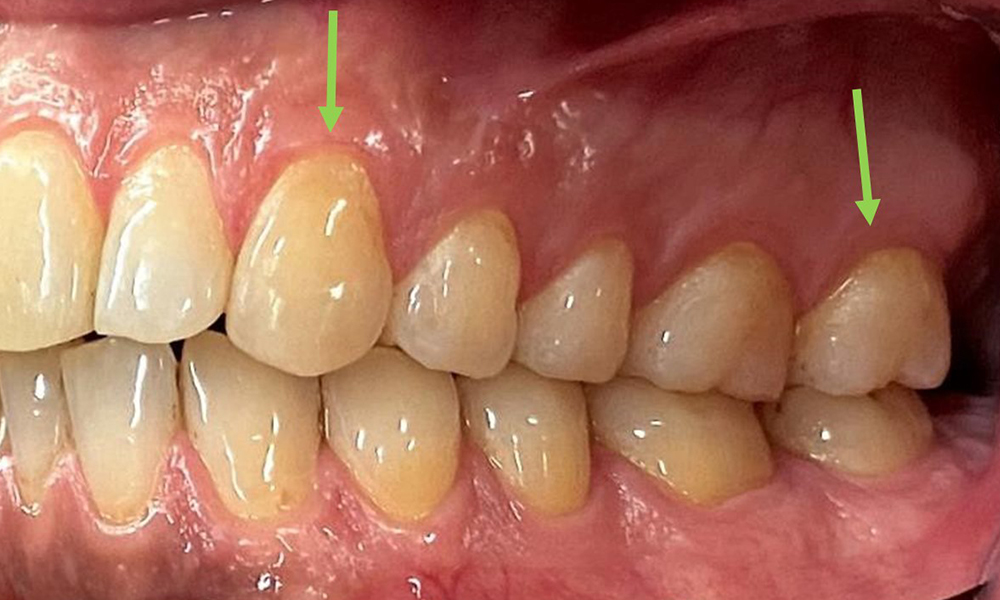

Close-up view of teeth

Fig. 5: Close-up view of teeth 45 to 47. The green arrows show dental attrition and erosions of the buccal cusps with partial enamel loss, © Dr R. Krapf

The patient has full dentition with a total of 28 teeth. There were noteworthy erosions and attritions. (Fig. 4, Fig. 5). Due to bruxism, the patient has been wearing a splint with an adjusted bite block at night for many years. The erosions were caused by long-term consumption of isotonic beverages. No periodontal bone loss or active caries were observed.

At 1 to 3 mm, the clinical probing depths were within the physiological range. Maxillary recessions of up to 1 mm were observed from 13 to 16 and 23 to 27. The BOP was 15%.